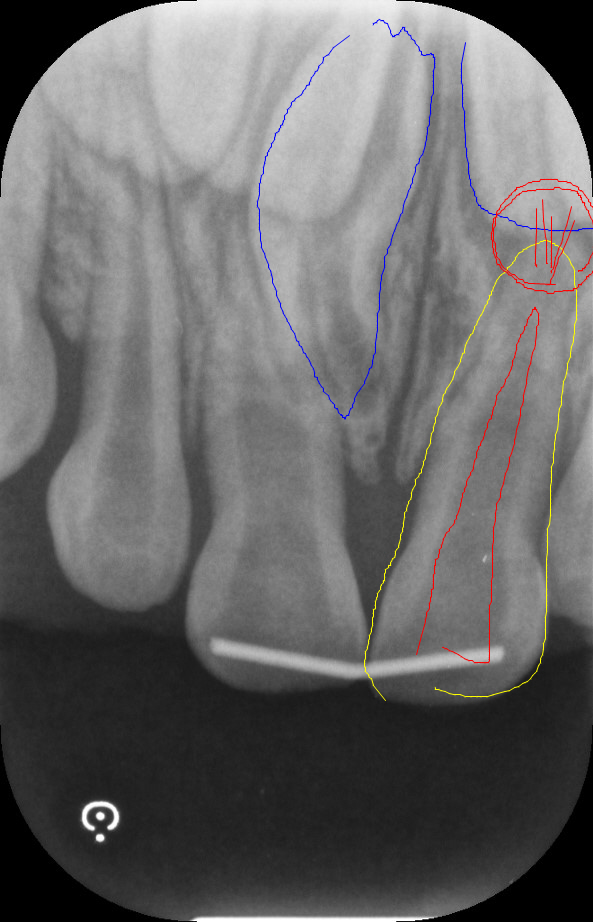

今回のように歯茎から出血している時は、歯の根元が折れてしまっていることが考えられるので、レントゲンで状態を確認する必要があります。

レントゲンを確認すると・・歯槽骨骨折、歯肉の挫滅

まず最初にレントゲンを撮り、歯の根っこと骨の状態を確認します。

今回のケースでは転倒の衝撃で、骨に大きなダメージが加わって歯の根元が折れてしまっていました。

軽い動揺であれば安静にして様子を見ますが、今回は明らかな動揺が見られましたので両脇の歯と一緒に固定をすることにいたしました。

両脇の歯と共に固定

歯が保存可能の場合はこの状態で2か月間ほど様子を見ます。 しかし歯根が破折していたり歯が斜めに折れてしまっていると残念ながら抜歯になってしまう可能性があります。